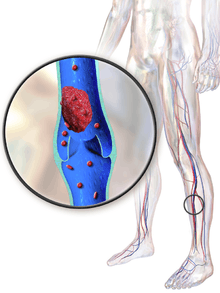

Deep vein thrombosis, or deep venous thrombosis, (DVT) is the formation of a blood clot (thrombus) within a deep vein,[lower-alpha 1] most commonly the legs. Nonspecific signs may include pain, swelling, redness, warmness, and engorged superficial veins. Pulmonary embolism, a potentially life-threatening complication, is caused by the detachment (embolization) of a clot that travels to the lungs. Together, DVT and pulmonary embolism constitute a single disease process known as venous thromboembolism. Post-thrombotic syndrome, another complication, significantly contributes to the health-care cost of DVT.

Common signs and symptoms of DVT include pain or tenderness, swelling, warmth, redness or discoloration, and distention of surface veins, although about half of those with the condition have no symptoms.[1] Signs and symptoms alone are not sufficiently sensitive or specific to make a diagnosis, but when considered in conjunction with known risk factors, can help determine the likelihood of DVT.[2] In most suspected cases, DVT is ruled out after evaluation,[3] and symptoms are more often due to other causes, such as cellulitis, Baker's cyst, musculoskeletal injury, or lymphedema.[4] Other differential diagnoses include hematoma, tumors, venous or arterial aneurysms, and connective tissue disorders.[5]